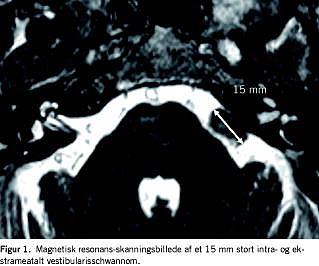

I henhold til international klassifikation [20 ] blev tumorerne kategoriseret enten som rent intrameatale eller som både intra- og ekstrameatale. Afhængig af den største ekstrameatale diameter blev tumorerne inddelt i følgende grupper efter størrelse: intrameatale 0 mm, små 1-10 mm, medium 11-20 mm, moderate 21-30 mm, store 31-40 mm og meget store tumorer med en ekstrameatal diameter større end 40 mm (Figur 1 ). Definitionen af signifikant vækst i gruppen af intrameatale tumorer var vækst til ekstrameatal udbredelse, i gruppen af intra- og ekstrameatale tumorer var vækst defineret som mindst 3 mm øgning af den største ekstrameatale diameter mellem den diagnostiske og den sidste CT/MR-skanning. I tilfælde af signifikant vækst blev patienten anbefalet at lade sig behandle enten med kirurgi eller strålebehandling.